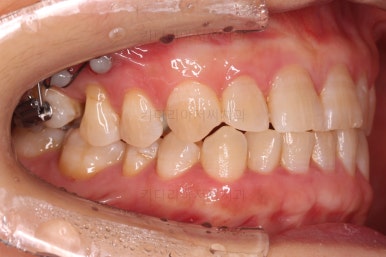

어금니를 뒤로 밀어주기 위해서 미니스크로와 브라켓, 철사를 이용해줍니다.

중간중간 장치 디자인이나 미니스크류의 위치를 바꿔주기도 합니다.

점점 자리가 확보되어가는게 보이시죠?

적절한 공간이 확보되었다고 판단되면 임플란트를 식립합니다.

임플란트가 뼈에 단단히 붙은 몇개월의 시간동안 교정치료를 좀 더 마무리 해주고요.

임플란트 머리 부분까지 완성이 되었습니다.

교정치료와 임플란트를 병행하면서 치아 빠진 부위가 다행히 잘 마무리가 되었네요.

전후사진을 비교해보겠습니다.

쓰러진 치아도 원위치로 만들어 기능을 회복시켜주었고, 임플란트도 1개로 마무리를 할 수 있었어요.